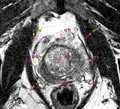

• Loadable module to simplify user-guided interactive segmentation has been developed. The workflow consists of two steps:

• Initialization: user provides B-spline transformation, the fixed and moving fiducial grids are initialized based on the configuration of the B-spline control point grid over the image.

• Adjustment: user can iteratively change the locations of the moving fiducials, and apply deformable registration (Landwarp is wrapped by the module).